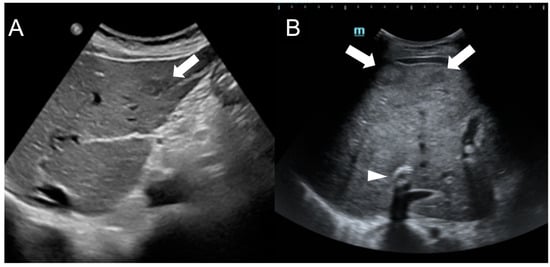

In US imaging, FNH-like RNs are often heterogeneous, but they may also appear isoechoic [31] and become challenging to detect in cases where the background liver parenchyma is altered due to congestion or fibrosis (Figure 5). Hypervascularity on Doppler flow imaging and peripheral hypoechoic rim were very common findings, but lack the specificity to distinguish regenerative nodules from malignant lesions. Contrast-enhanced ultrasound (CEUS) offers valuable support in the detection and characterization of focal liver lesions in BCS [32,33]. After intravenous administration of microbubbles, around 70% of FNH-like RNs demonstrate a rapid center-to-periphery hyperenhancing filling in the arterial phase, with one-third displaying a characteristic “spoke wheel” aspect. In the portal and delayed phases, nearly 90% of FNH-like RNs maintain consistent and homogeneous hyperenhancement, while the rest show enhancement similar to the background liver parenchyma. These features differ from those of HCC nodules, as they more commonly show washout in the portal and venous phases.

Figure 5.

Ultrasound images of a 59-year-old female patient (A) and a 34-year-old male patient (B) with Budd-Chiari syndrome. In both cases, FNH-like RNs appear as hypoechoic lesions (arrows) within the heterogeneous liver parenchyma, occasionally exhibiting a central hyperechoic scar. A TIPS stent is visible in case B (arrowhead).